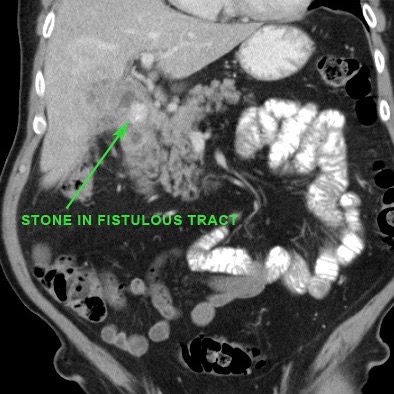

Viêm túi mật không được chẩn đoán hoặc không được điều trị cũng có thể dẫn đến hình thành đường rò vào tá tràng.

Đây là một biến chứng không thường gặp, nhưng khi xảy ra, hầu hết các trường hợp sỏi sẽ di chuyển vào ruột non, nơi sỏi bị kẹt lại và gây ra tắc ruột do sỏi mật.

Trong các trường hợp hiếm gặp của rò tá tràng, một viên sỏi mật lớn có thể bị “kẹt” tại đường rò vào tá tràng.

Do mô viêm và mô xơ thứ phát, tình trạng này có thể dẫn đến hẹp và tắc nghẽn.

Tình huống đặc biệt này được gọi là “hội chứng Bouveret” với biểu hiện lâm sàng chính là tắc nghẽn đường ra dạ dày.

Trong các trường hợp hiếm gặp của rò tá tràng, một viên sỏi mật lớn có thể bị “kẹt” trong quá trình rò kéo dài.

Do mô viêm và mô xơ thứ phát, tình trạng này có thể dẫn đến hẹp và tắc nghẽn tá tràng.

Tình huống đặc biệt này được gọi là “hội chứng Bouveret” với biểu hiện lâm sàng chính là tắc nghẽn đường ra dạ dày (hình).

Một viên sỏi lớn bị “kẹt” trong đường rò từ túi mật biến dạng đến tá tràng.

Dày thành tá tràng thứ phát (đầu mũi tên) cùng mô viêm và mô xơ xung quanh gây ra tình trạng ứ đọng dạ dày từng đợt kèm nôn mửa.